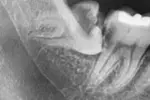

2025년 12월 16일 11:50 매복 사랑니 발치 난이도 어느정도 일까요 () 오른쪽은 뺐구요 사랑니가 바르게 나서 하나도 안았팠어요 왼쪽은 사랑니 안뺐는데 매복이라 겁나네요 사진 보시면 오른쪽 아래에 매복이 있는데 사진이 반대라서 왼쪽입니다 얼마나 빡셀까요 벌써부터 걱정이 드네요 이 게시물은 얼마나 유용했습니까? 별을 클릭하여 등급을 매깁니다! 평가 제출 평균 평점 / 5. 투표 수: 지금까지 투표가 없습니다! 이 게시물을 평가하는 첫 번째 사람이 되세요. 신고하기 이름: 이메일: 신고 내용: 제출하기 Related posts: 사랑니 발치 난이도 어때보임? 이런 것도 PPL 일까요? 여기 이전하면 땅값 가치가 어느정도 일까요? 모카에서 중국 전기차 자율주행 기술이 좋다던데 사실 일까요? 어려서부터 한국에 산 외국인들은 이상형도 한국인 일까요 도대체 특정 사람들 음모론의 끝은 어디까지 일까요. 배우 이세영 실제 키가 어느정도 일까요?.JPG 사랑니 발치 난이도 어때보이나요?